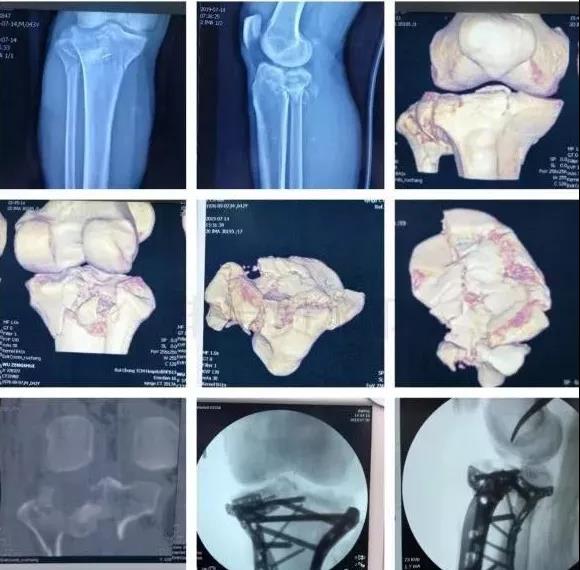

7)胫骨远端(pilon,踝部)

- pilon骨折,高能损伤,6-8h肿胀未形成,可以急诊做,手术时间<3小时。

- 10-14天,分步延期手术策略。

- 踝部骨折手术时机同样取决于皮肤条件。